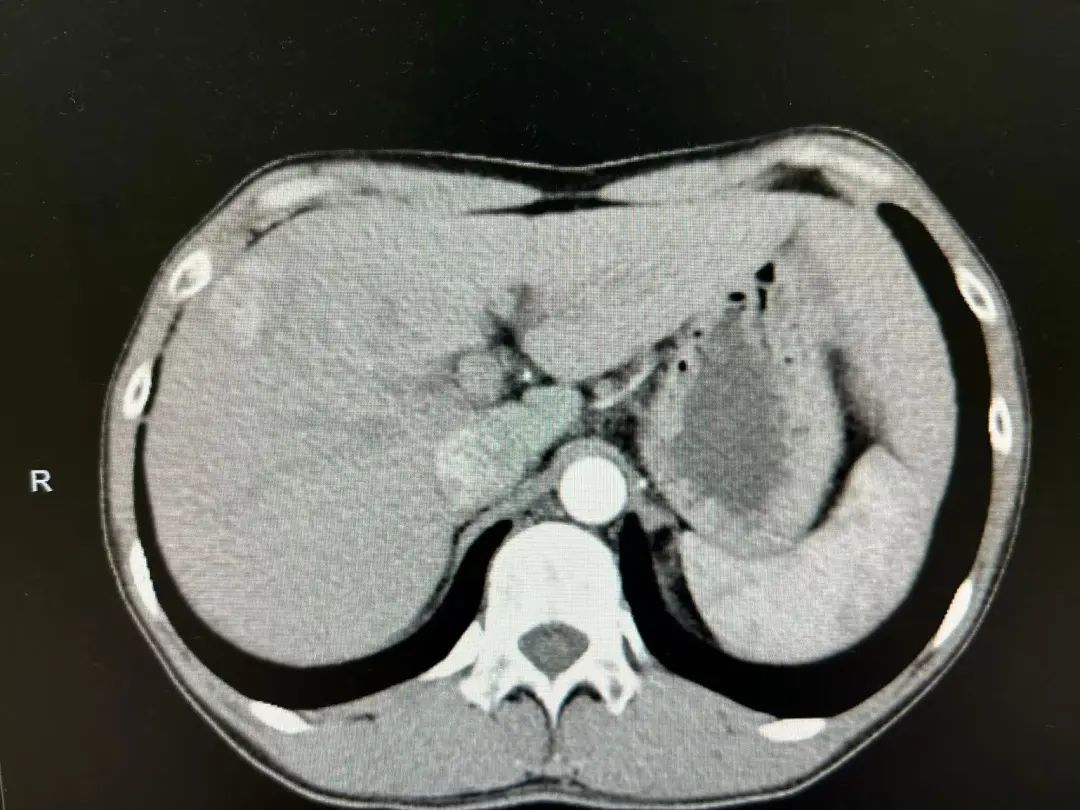

34岁的张先生(化名)在事业上升期却突遭“肝占位性病变”诊断,肿瘤位于肝脏最深、最难到达的S8段——这一部位被誉为腹腔镜肝切除的“珠峰区域”,手术难度极大。面对挑战,我院普外科团队与麻醉科、影像科等多学科协作,量身定制腹腔镜下精准肝S8段切除方案。团队在普外科朱振飞主任带领下,凭借三维立体解剖认知和高超腔镜操作,将复杂手术转化为精密“拆弹”,最大程度保障了手术安全与疗效。高清腹腔镜系统将肝脏结构放大数倍,配合超声刀等先进器械,实现精准切割与有效止血。传统开腹手术常伴随大创伤和长恢复期,而微创方案则以最小损伤换取最大健康,让患者在保留更多健康肝组织的同时,实现根治目标。

在普外科周明副主任医师的精细操作下,手术团队将肝脏肿瘤周围直径 3mm范围内的小动脉、肝静脉、门静脉、小胆管逐一结扎,完整切除肿瘤。术中,麻醉团队与手术团队默契配合,将出血量严格控制在 50ml,较同类手术500-1000ml的出血量大幅下降。这一成果不仅展现了普外科团队精湛的技术实力,更凸显了多学科协作在高难度微创手术中的关键作用。